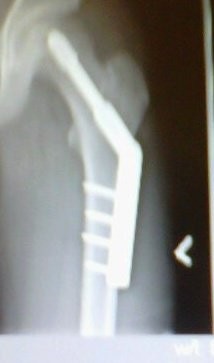

second ride back from breaking both wrists I had quite the life changer..